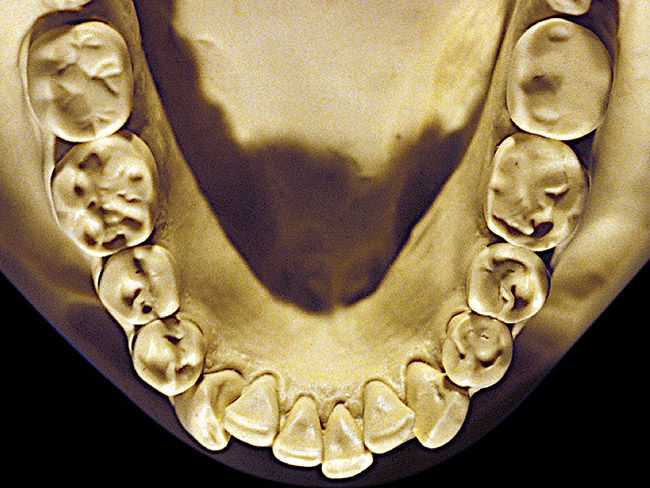

Figure 12  Advanced NCLTS from toothpaste, mandibular arch.

Figure 12

So that the previous example is not misleading, the behavioral profile of the toothpaste abuser is not necessarily the "caries-free immaculate oral hygiene patient," but can be virtually anyone who brushes their teeth with toothpaste. Figure 11 and Figure 12 illustrate a more advanced example of toothpaste abuse showing a patient with multiple restorations and some unkempt teeth. The anatomical details were faded with a sandblasted appearance and the silver alloy restorations were highly polished. The facial surfaces of the mandibular canines and premolars were affected the most, creating the pathognomonic pattern. Figure 13 and Figure 14 are a close-up view of this area, illustrating a cupping or cratering effect, but of the asymmetrical variety. This patient did not like the color of his teeth and spent an inordinate amount of time brushing his teeth. Again, likewise due to the exclusive use of a round-ended, soft-bristle toothbrush, note there was no cervical gingival recession in this case either. When the featured casts illustrating toothpaste abuse (Figure 7, Figure 8, Figure 9, Figure 10, Figure 11, Figure 12, Figure 13 and Figure 14) were hand-articulated, the worn surfaces did not match up and the diagnosis of toothpaste abuse was confirmed.